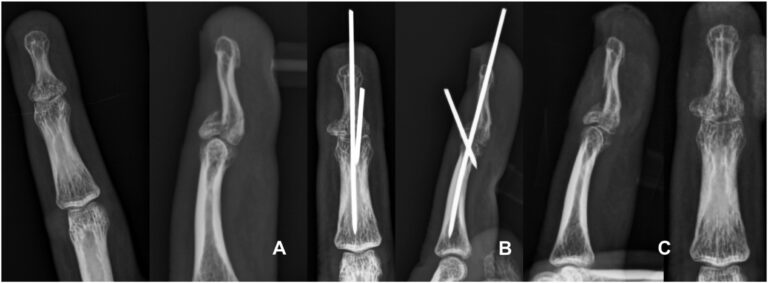

La colocación de clavos en bloque de extensión percutánea es una de las modalidades de tratamiento para las lesiones óseas desplazadas en martillo. Se han descrito varias modificaciones técnicas con una o más agujas de Kirschner. El propósito de este estudio es analizar los resultados de la fijación con alambre de Kirschner dorsal específico de un fragmento para las fracturas en martillo.

- Sugerimos la primera aguja de Kirschner como paso clave para la reducción de fragmentos de fracturas.

- Aguja de Kirschner de lados radiales para desplazamiento dorso-radial.

- Un lado cubital para el desplazamiento dorso-cubital.

- Dos agujas de Kirschner dorsales paralelas para el fragmento central.